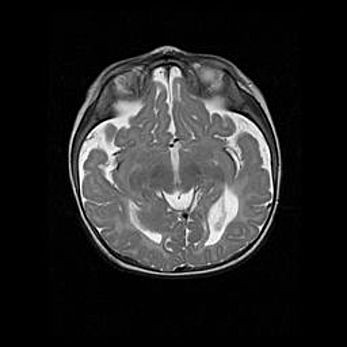

Лейкомаляция с кистозно-глиозной дегенерацией головного мозга.

Возраст: 2 месяца 25 дней

Вес: 6400 г

Окружность головы: 40 см

Срок гестации: 41 неделя

Лейкомаляцию относят к ишемически-гипоксическим повреждениям головного мозга, диагностируемым у новорожденных. При лейкомаляции в головном мозге обнаруживают очаги некроза, возникшие после тяжелой гипоксии и нарушения кровотока. В процессе морфогенеза очаги проходят три стадии: 1) развития некроза, 2) резорбции и 3) формирования глиозного рубца или кисты. Перивентрикулярная лейкомаляция (ПЛ) встречается примерно в 12% случаев среди новорожденных, обычно – у недоношенных детей, причем, частота ее зависит от массы, с которой младенец появился на свет. Наибольшее число малышей страдает лейкомаляцией, если масса при рождении 1500-2500 г.